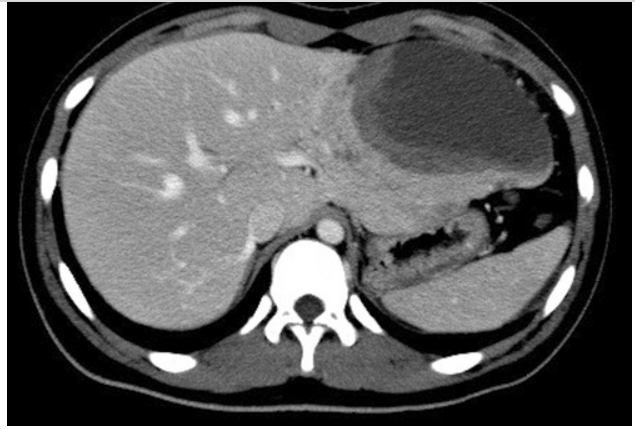

患者为一名15岁男孩,因腹痛就诊。影像学检查显示肝左外叶存在一个巨大肿瘤,大小约为12 *8*6 cm(图1)。

图1. 腹部增强CT扫描显示,肝脏左外侧叶有一个低密度肿块(12 × 8 × 6 cm),强化不良,位于左肝叶外侧段

初步检查未发现远处转移。鉴于肿瘤局限且患者年龄较大,临床首先怀疑为HCC,遂行系统的左肝外叶切除术,实现了肿瘤的完整切除(R0切除)。